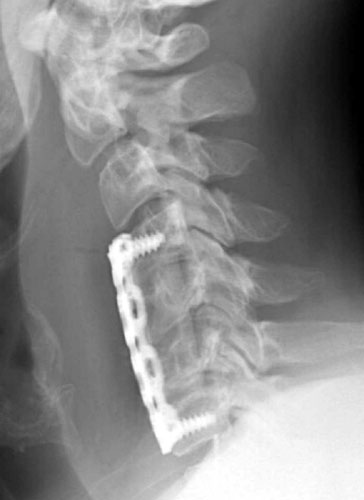

The patient is a 46-year-old male who had undergone the corpectomies of C5-6

and discectomies at C4-7 with anterior plate fusion and bone grafting for

cervical myelopathy resulting from cervical stenosis as well as kyphotic

deformity. Thereafter, the patient noted increased spasm of his right arm as

well as right leg. Work up revealed that the patient had dislodged the inferior

portion of the bone graft as well as the plate.

This post-operative radiograph suggests normal alignment of the bone graft

and fixation plate